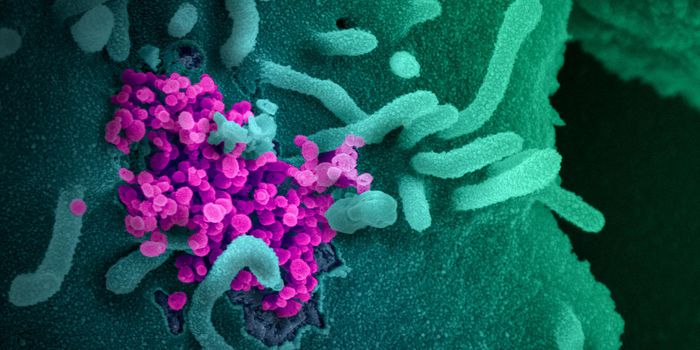

JAN 01, 2021CardiologyScientists have been trying to determine if the SARS-CoV-2 virus infects brain cells directly, or if the virus severely ...

JUN 29, 2021ImmunologyResearchers at the Washington University School are getting to the root of heart damage resulting from COVID-19 infectio ...